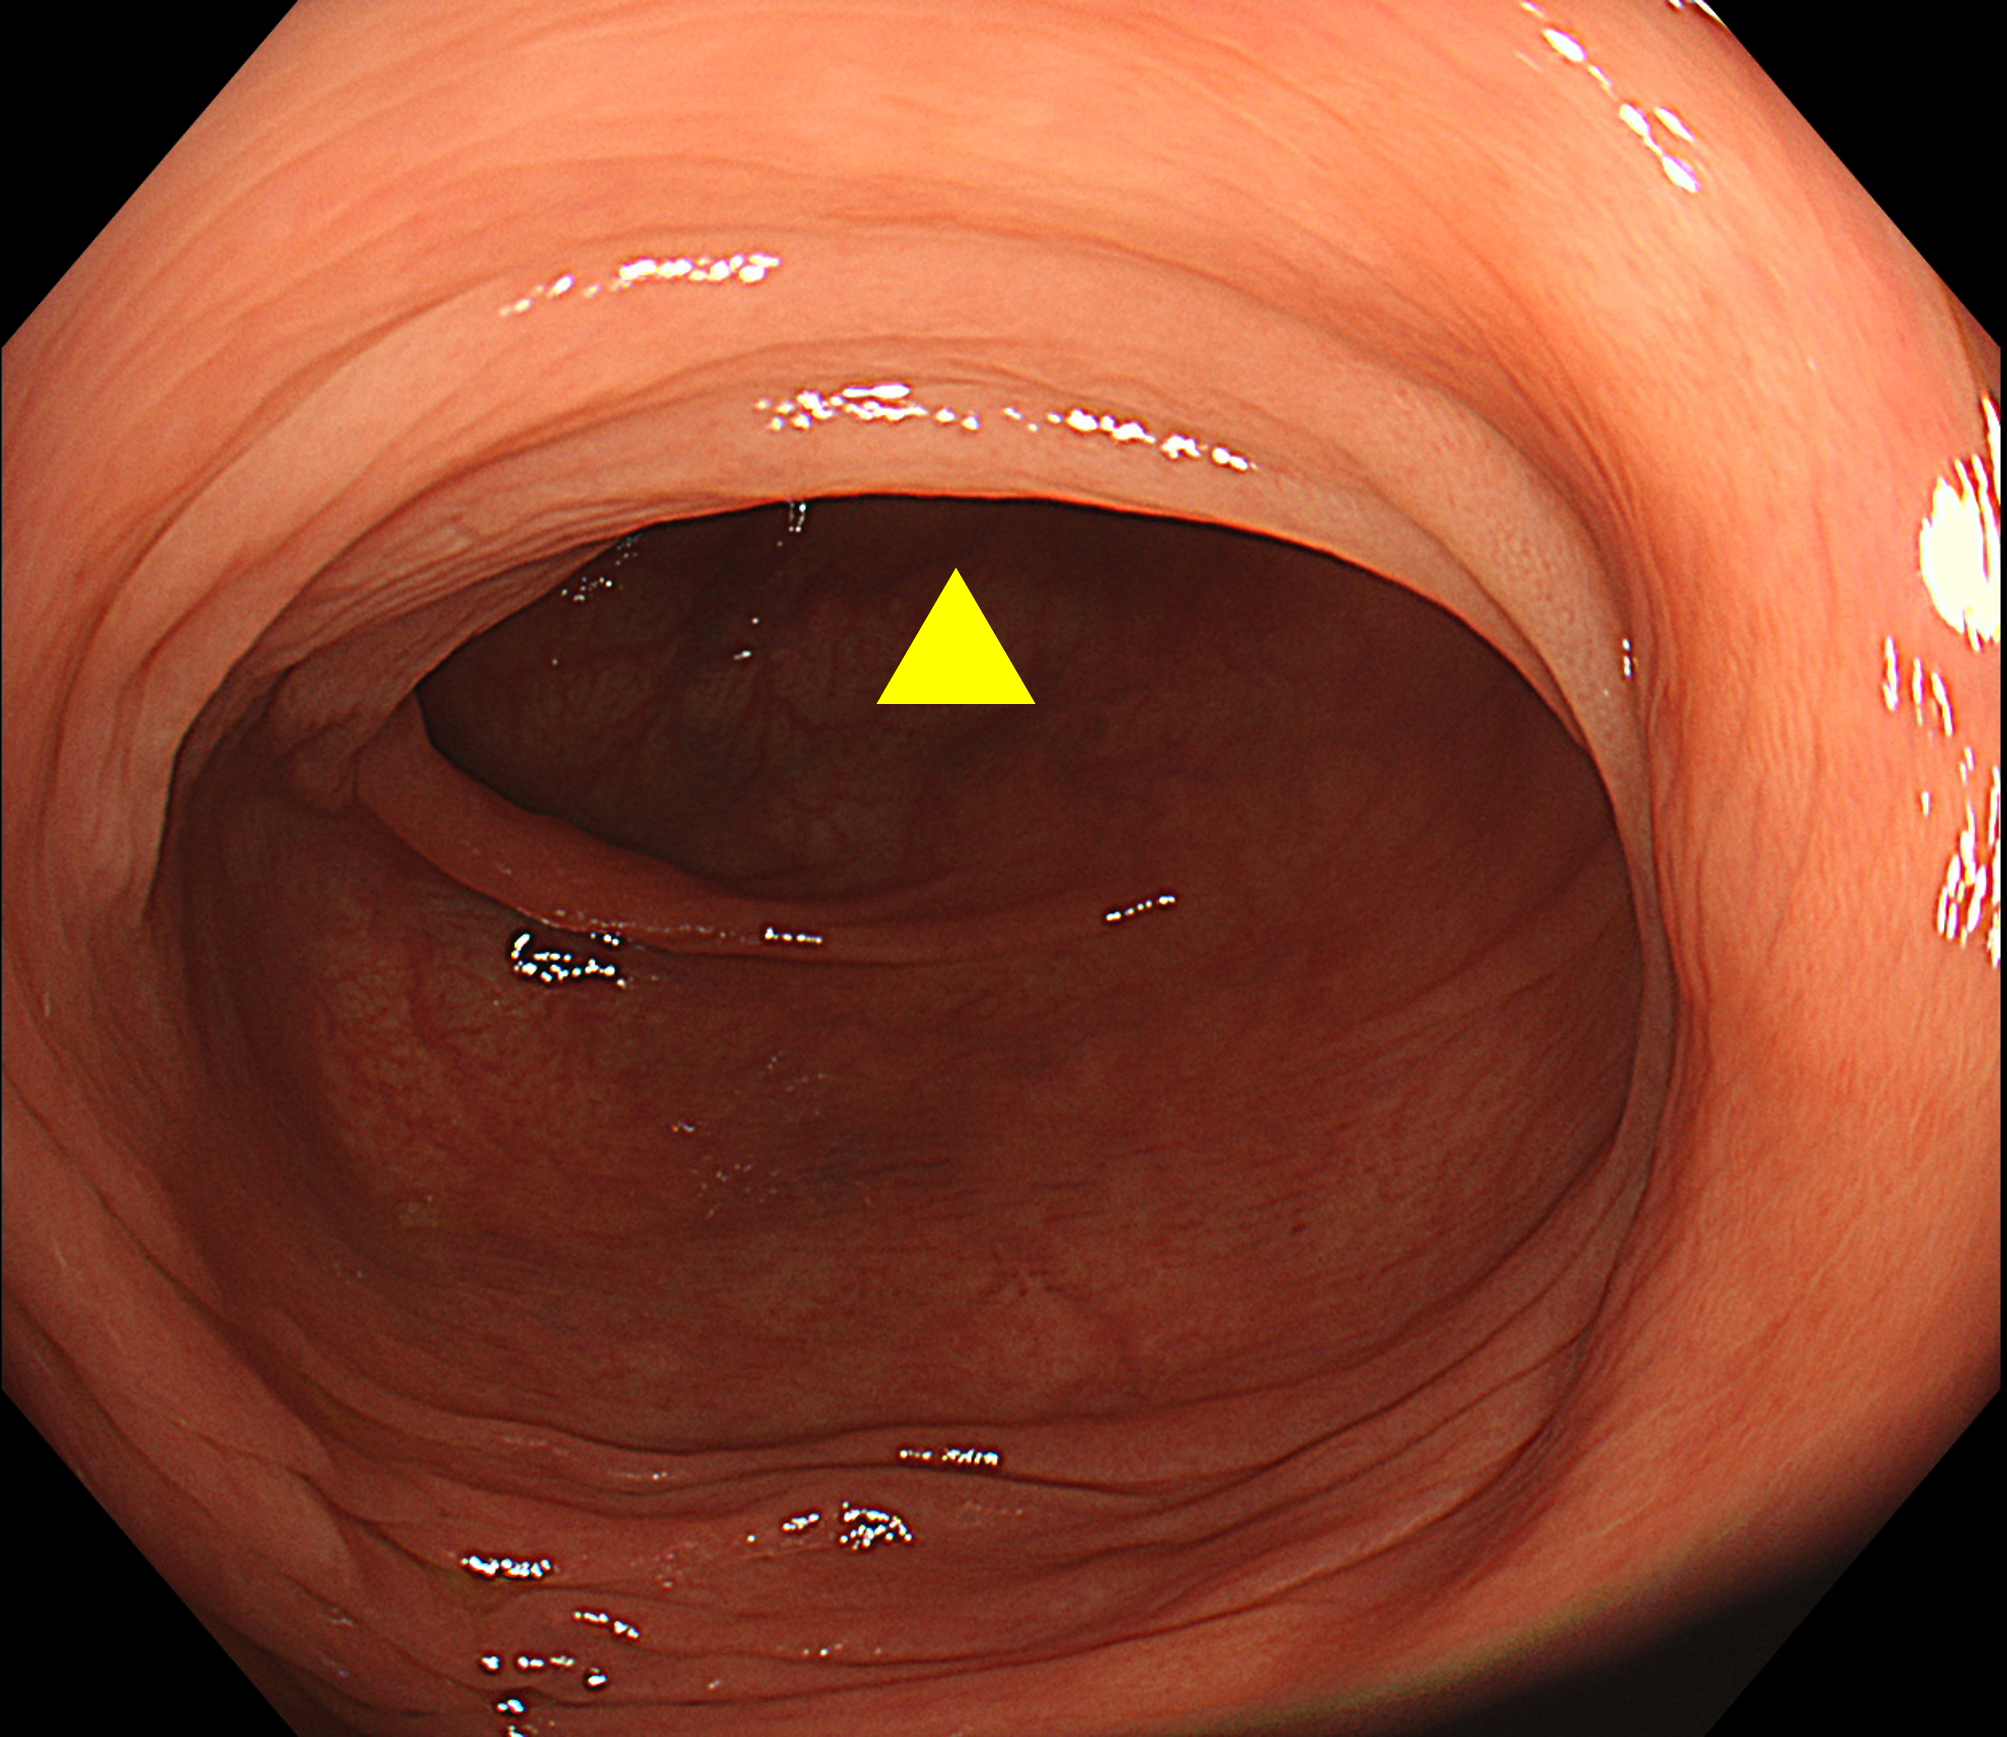

盲腸では、虫垂開口部周囲や回盲弁の裏側が死角となりやすい(※Figure1)。盲腸底部から全体を俯瞰するように観察し、回盲弁は唇裂部を意識して十分に送気・近接観察を行うことが重要である(※Figure2)。

• ※Figure 2. 回盲弁下唇裏側にある0-Ⅱa病変

(a) 回盲弁正面視(病変は見えない)

•

(b) 回盲弁下唇裏側をめくるように観察